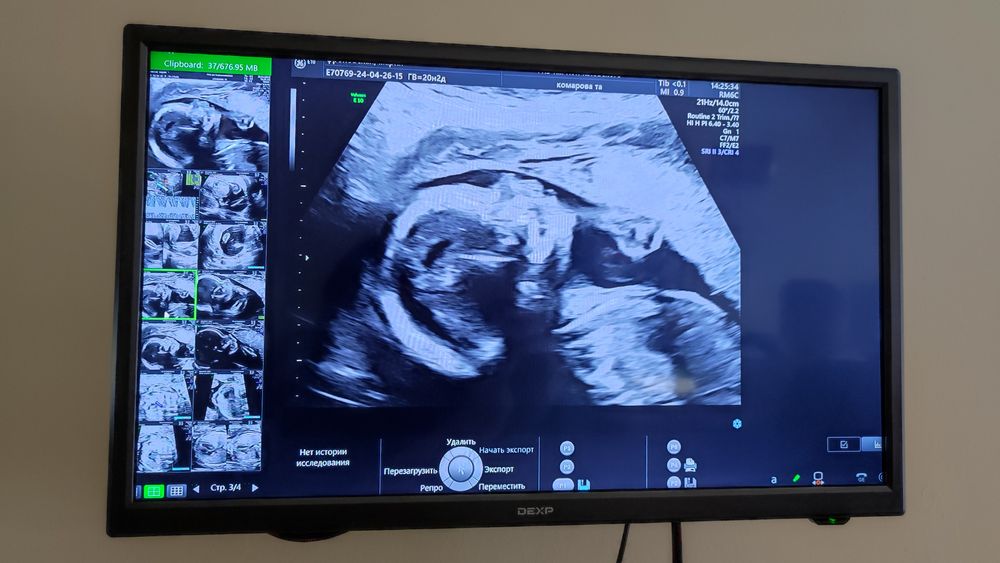

В остальное всё очень хорошо прошло. Приятно, что поставили дополнительный экран, на котором мама может наблюдать за измерениями малыша. Мой вот оказался не таким уж сговорчивым, пришлось покрутиться несколько раз, чтоб его растормошить, а то зажимался, ручку в кулачках держал. Место прикрепления пуповины так и не увидела врач, но его было видно на первом скрининге, так что не страшно. И написали ещё неустойчивое положение плода, что это значит? Не поставили ни головной, ни тазовое предлежание, или для этого рано ещё? Меня всё беспокоило количество вод. Написали 12,1 см, это норма? Не маловодие? На УЗИ казалось что как то мало места малышу, или это просто по моему незнанию 😂

И профиль малыша мне очень понравился, такой красивый 😍